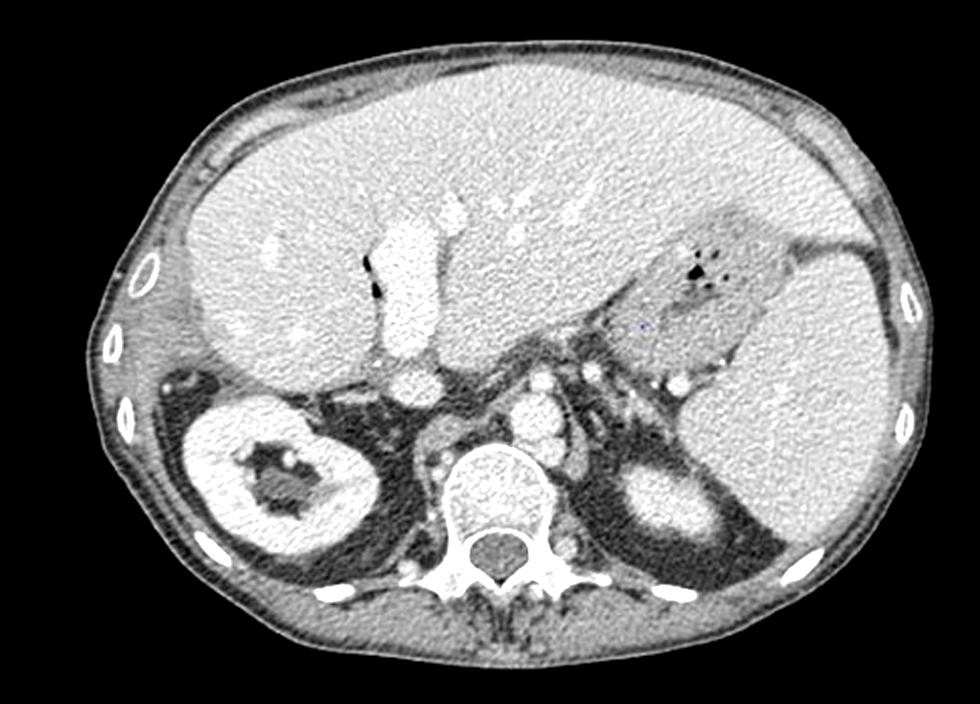

In October 2021 her CT scan revealed a cirotic liver with important portal hypertension (fig. 7).

Figure 7 - CT scan - cirrhotic liver with important portal hypertension (October 2021)